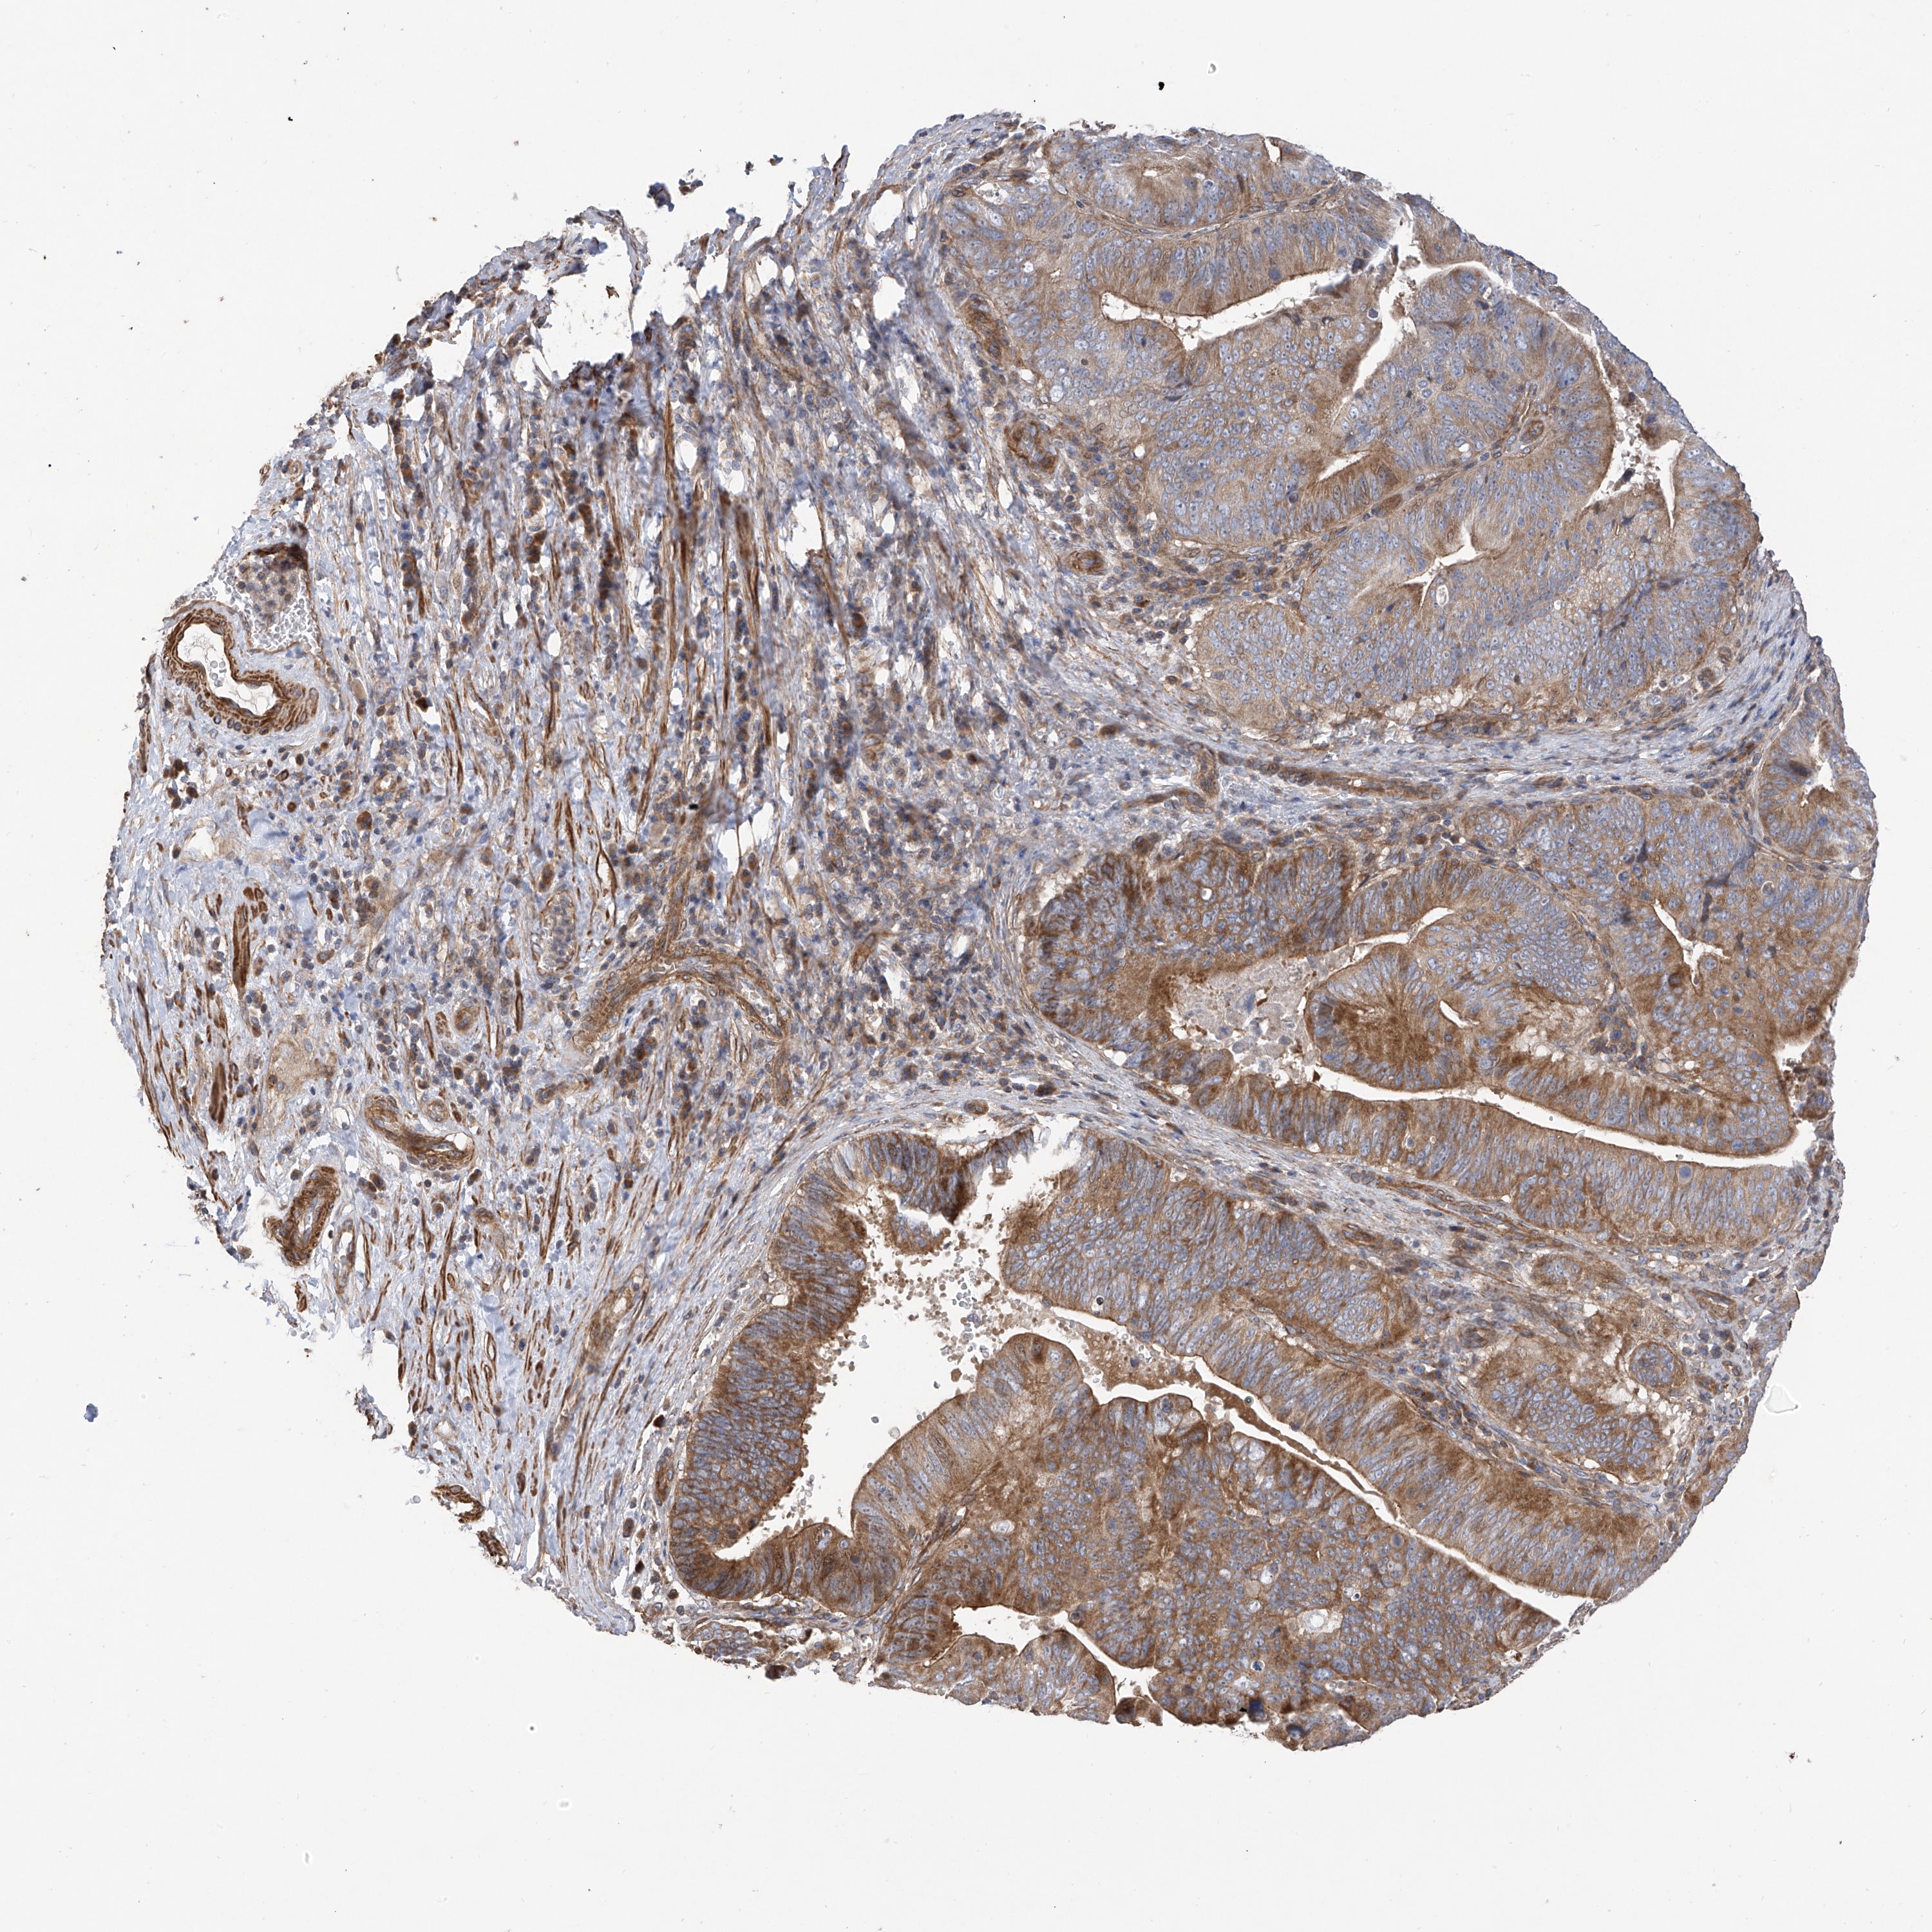

PANCREATIC CANCER - Protein expressioni

A mouse-over function shows sample information and annotation data. Click on an image to view it in a full screen mode. Samples can be filtered based on level of antibody staining by selecting one or several of the following categories: high, medium, low and not detected. The assay and annotation is described here.

Note that samples used for immunohistochemistry by the Human Protein Atlas do not correspond to samples in the TCGA dataset.

Antibody stainingi

Antibody staining in the annotated cell types in the current human tissue is reported as not detected, low, medium, or high, based on conventional immunohistochemistry profiling in selected tissues. This score is based on the combination of the staining intensity and fraction of stained cells.

Each image is clickable and will lead to virtual microscopy that enables deeper exploration of all samples and also displays staining intensity scores, fraction scores and subcellular localization as well as patient and tissue information for each sample.

Antibody HPA030551

Staining

High

Medium

Low

Not detected

Intensity

Strong

Moderate

Weak

Negative

Quantity

>75%

75%-25%

<25%

None

Location

Nuclear

Cytoplasmic/membranous

Cytoplasmic/membranous,nuclear

Adenocarcinoma, NOS